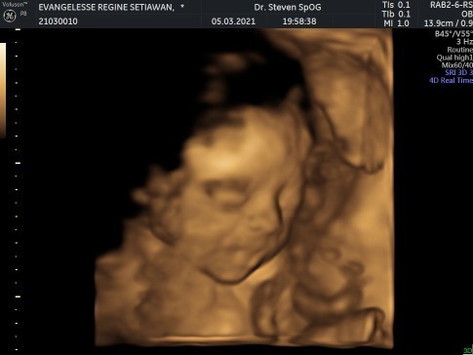

Halo semuaaa. Ini hasil USG baby girl ku memasuki usia kandungan 7 bulan. HPL awal Juni 2021 nih, ada yg sama? Semua keadaan baik, perkembangannya bagus, ketuban banyak, bb dan pb janin cukup. Kata dokter hidungnya mancung hihi. Cuma baby nya masih sungsang, kepala masih di atas. Ya sudah gpp, yg penting semua keadaan baik dan sehat. Gimana bunda" yg lain? Ada yg baru USG juga? Mudah"an semua sehat dan diberi kelancaran ya sampai hari lahir nanti ☺️ #firstbaby #bersyukur #feelsoblessed #semangat